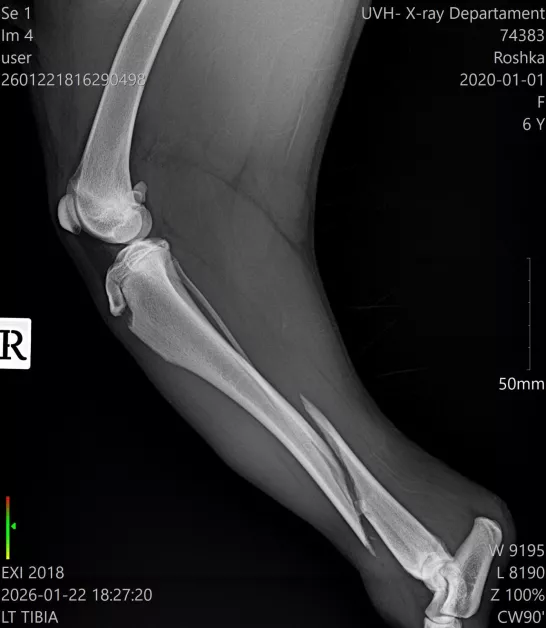

Диагнозата е тежка – две съществени фрактури на задните крака в региона на пищялите, с разбъркване и травмирани меки тъкани. По думите на ортопеда съществува действителен късмет фрактурите да бъдат закрепени с импланти и винтове, което би разрешило на Рошка още веднъж да проходи.